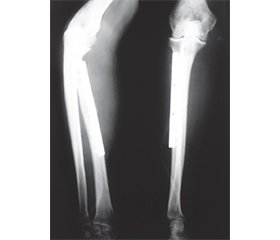

Актуальність. Злоякісні пухлини кісток передпліччя зустрічаються рідко і лишаються проблемою для онкологів-ортопедів. У нашому дослідженні повідомляється про доброякісні місцевоагресивні та злоякісні пухлини кісток передпліччя та різні стратегії хірургічного видалення пухлин і методики реконструкції кісток. Вибір хірургічного втручання при ураженні кісток передпліччя зумовлений не тільки ступенем руйнування кістки пухлиною та нозологічною формою пухлинного процесу, але й здатністю до рецидивування та метастазування пухлини. Проведено аналіз функціональних та онкологічних результатів верхньої кінцівки після комплексного та комбінованого лікування пухлин кісток передпліччя. Мета: показати ефективність комбінованого та комплексного лікування доброякісних місцевоагресивних і злоякісних пухлин кісток передпліччя. Матеріали та методи. Під нашим спостереженням перебували пацієнти (n = 27) із пухлинами кісток передпліччя. Було 17 (62,9 %) пацієнтів із пухлинами променевої кістки та 10 (37,1 %) — із пухлинами ліктьової кістки, 16 (59,2 %) — із гігантоклітинною пухлиною кістки, тоді як 11 (40,8 %) мали злоякісні пухлини. Спостереження у середньому становило 27 (від 6 до 42) місяців. Усім 27 пацієнтам були виконані хірургічні втручання у схемах комбінованого та комплексного лікування. Резекція променевої кістки виконана у 17 хворих, причому найчастіше дистального відділу (13 пацієнтів), проксимального відділу (3), діафіза кістки (1). У 10 хворих виконали резекцію ліктьової кістки, причому найчастіше проксимального відділу ліктьової кістки (5 пацієнтів), дистального відділу (3), діафіза кістки (2). Хірургічні межі пухлини після резекції кістки з пухлиною при морфологічному дослідженні були по краю ураження у 2 пацієнтів. Результати. Післяопераційні ускладнення спостерігалися у 3 (11,1 %) хворих. Функціональні результати верхньої кінцівки після органозберігаючих операцій із приводу пухлин кісток передпліччя за шкалою MSTS становили: після ендопротезування ліктьового суглоба — 74,8 %, після кістково-пластичної операції проксимального відділу ліктьової кістки із застосуванням алотрансплантату та керамічного матеріалу на основі біоактивного скла функція ліктьового суглоба — 96,6 %; після резекції діафіза ліктьової кістки й армованого металоостеосинтезу — 94,5 %; після резекції дистального відділу ліктьової кістки з пухлиною функція променево-зап’ясткового суглоба — 80,4 %; після резекції дистального відділу променевої кістки з пухлиною й автопластики малогомілковою кісткою функція променево-зап’ясткового суглоба — 88,3 %; після резекції дистального відділу променевої кістки з пухлиною й ендопротезування металоцементним імплантом функція променево-зап’ясткового суглоба — 84,2 %; після резекції проксимального відділу променевої кістки з пухлиною функція верхньої кінцівки — 78,5 %; після резекції діафіза променевої кістки й армованого металоостеосинтезу функція кінцівки — 98,4 %. Онкологічні результати: місцевий рецидив пухлини спостерігався у 3 пацієнтів (11,1 %), віддалені метастази — у 3 (7,4 %). Трирічна загальна виживаність хворих становила 82,4 ± 7,6 %, трирічна безрецидивна виживаність — 76,6 ± 8,5 %. Висновки. Рецидив пухлини кістки пов’язуємо з неадекватною відповіддю пухлини на проведені у передопераційний період курси поліхіміотерапії та променевої терапії, а також із нерадикальним видаленням (недодержанням хірургічних меж пухлини під час резекції кістки) пухлини. Віддалені метастази є наслідком рецидиву пухлини після проведеного комплексного та комбінованого лікування та поганим прогностичним фактором виживаності пацієнтів.

Background. Malignant tumors of the forearm bones are rare, and remain a problem for orthopedic oncologists. Our study reports on benign locally aggressive and malignant tumors of the forearm bones, and various strategies for surgical removal of tumors, and bone reconstruction techniques. The choice of surgical intervention in case of the diseased forearm bones is determined not only by the degree of bone destruction by the tumor and the nosological entity of the neoplastic process, but also by the ability of the tumor to recur and metastasize. An analysis of the functional and oncological results of the upper limb after comprehensive and multimodal treatment of tumors of the forearm bones was conducted. Purpose. to show the effectiveness of multimodal and comprehensive treatment of benign locally aggressive and malignant tumors of the forearm bones. Materials and methods. Patients (n = 27) with tumors of the forearm bones were under our observation. There were 17 (62.9 %) patients with radial bone tumors and 10 (37.1 %) patients with ulna tumors, 16 (59.2 %) patients had giant cell tumor of bone, while 11 (40.8 %) had malignant tumors. The average follow-up lasted 27 (range 6 to 42) months. All 27 patients underwent surgical interventions within multimodal and comprehensive treatment regimens. Radial bone resection was performed in 17 patients, at that, most often of distal segment (13 patients), of proximal segment (3 patients), and of diaphysis of bone (1 patient). Ulnar bone resection was performed in 10 patients, at that, most often of proximal ulna (5 patients), of distal ulna (3 patients), and of diaphysis of bone (2 patients). The surgical margin of the tumor, after resection of the bone with the tumor, during morphological examination were along the edge of the lesion in 2 patients. Results. Postoperative complications were observed in 3 (11.1 %) patients. Functionality results of the upper limb after organ sparing surgery for tumors of the forearm bones according to the MSTS scale were: after the elbow joint endoprosthesis replacement the function amounted to 74.8 %, after osteoplastic surgery of the proximal ulna using allograft and ceramic material based on Bioactive Glass, the function of the elbow joint amounted to 96.6 %. After resection of the ulna diaphysis, and effecting reinforced metallic osteosynthesis, it amounted to 94.5 %. After resection of the distal ulna with the tumor, the function of the radiocarpal joint amounted to 80.4 %. After resection of the distal radius with tumor, and effecting fibular bone grafting, the function of the radiocarpal joint amounted to 88.3 %. After resection of the distal radius with tumor, and effecting endoprosthesis replacement using a metal-cement implant, the function of the radiocarpal joint amounted to 84.2 %. After resection of the proximal segment of radius with tumor, the function of the upper limb amounted to 78.5 %. After resection of the radial diaphysis, and effecting reinforced metallic osteosynthesis, the function of the limb amounted to 98.4 %. Oncological results: local tumor recurrence was observed in 3 patients (11.1 %), distant metastases were observed in 2 patients (7.4 %). Three-year overall survival of patients amounted to 82.4 ± 7.6 %, three-year recurrence-free survival amounted to 76.6 ± 8.5 %. Conclusions. Bone tumor recurrence is associated with inadequate tumor response to preoperative courses of polychemotherapy and radiotherapy, as well as with non-radical tumor removal (failure to adhere to surgical tumor margins during bone resection). Distant metastases represent a consequence of tumor recurrence after comprehensive and multimodal treatment, and are an adverse prognostic factor for patient survival.